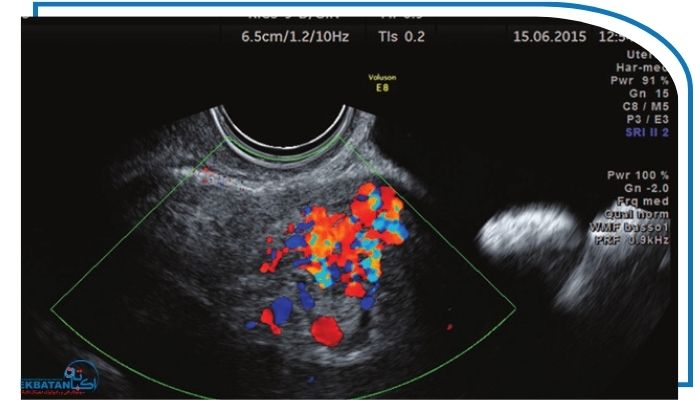

سونوگرافی داپلر نسخه پیشرفته‌ای از سونوگرافی معمولی است که علاوه بر نمایش ساختار اندام‌های داخلی سرعت و کیفیت جریان خون را نیز بررسی می‌کند. این تکنیک با استفاده از امواج فراصوت نشان می‌دهد خون چگونه در رگ‌های رحم و تخمدان‌ها حرکت می‌کند و آیا این جریان برای عملکرد طبیعی سیستم باروری مناسب است یا خیر.

از آنجا که نازایی یکی از چالش‌های مهم و رایج در زندگی بسیاری از زوج‌هاست استفاده از ابزارهای دقیق تصویربرداری برای تشخیص علت آن اهمیت زیادی دارد. یکی از مهم‌ترین این ابزارها سونوگرافی رنگی رحم است. این روش با ارزیابی جریان خون در رحم تخمدان‌ها، شریان‌های رحمی و حتی لایه اندومتر به پزشکان کمک می‌کند مشکلاتی را که با سونوگرافی معمولی قابل تشخیص نیستند شناسایی کنند. داپلر می‌تواند اختلالات پنهان در خون‌رسانی را آشکار کند؛ اختلالاتی که ممکن است مانع رشد مناسب فولیکول‌ها آماده‌شدن اندومتر برای لانه‌گزینی یا حتی موفقیت درمان‌های کمک‌باروری مانند IVF شوند.

در مقابل سونوگرافی رنگی علاوه بر نمایش ساختار جریان خون رحم و تخمدان‌ها را نیز ارزیابی می‌کند. جریان خون مناسب نقش اساسی در عملکرد هورمونی رشد درست فولیکول‌ها بلوغ تخمک و آماده‌شدن اندومتر برای لانه‌گزینی دارد. بنابراین داپلر کمک می‌کند تا مشکلات پنهانی مانند خون‌رسانی ضعیف تخمدان مقاومت بالای شریان‌های رحمی اندومتر کم‌خون‌رسان و اختلال در پاسخ هورمونی شناسایی شوند؛ مسائلی که به‌طور مستقیم بر کیفیت تخمک‌گذاری و شانس باروری تأثیر می‌گذارند.

سونوگرافی رنگی می‌تواند میزان خون‌رسانی در شریان‌های رحمی را به‌طور دقیق بررسی کند. زمانی که جریان خون در این شریان‌ها کم باشد اندومتر قادر به رشد طبیعی نیست و معمولاً نازک باقی می‌ماند. این مشکل باعث می‌شود اندومتر به داروهای تحریک تخمک‌گذاری پاسخ مناسبی ندهد و در نتیجه شانس لانه‌گزینی جنین کاهش پیدا ‌کند. بسیاری از موارد نازایی که علت مشخصی ندارند در واقع به دلیل همین اختلالات خون‌رسانی پنهان هستند که فقط با داپلر قابل تشخیص‌اند

داپلر با اندازه‌گیری جریان خون داخل فولیکول‌ها تصویر دقیقی از کیفیت آن‌ها ارائه می‌دهد. هرچه خون‌رسانی فولیکول بهتر باشد احتمال تولید یک تخمک سالم بیشتر است. این موضوع در درمان‌های کمک‌باروری مانند IVF اهمیت زیادی دارد زیرا پزشکان معمولاً فولیکول‌هایی را انتخاب می‌کنند که جریان خون قوی‌تری دارند تا کیفیت تخمک برداشت‌شده بالاتر باشد و شانس باروری افزایش یابد.